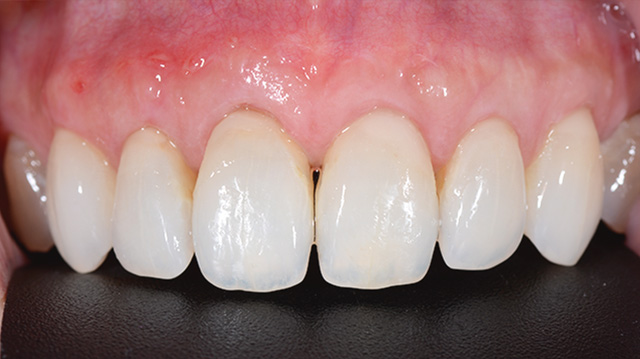

| 年代・性別 | 30代 女性 |

|---|---|

| 主訴 | 結婚式前に前歯を綺麗にしたい |

| 治療回数 | 3回 |

| 治療期間 | 約1ヶ月 |

| 費用 | 仮歯 5,500円 × 3 ジルコニアクラウン 176,000円 × 3 |